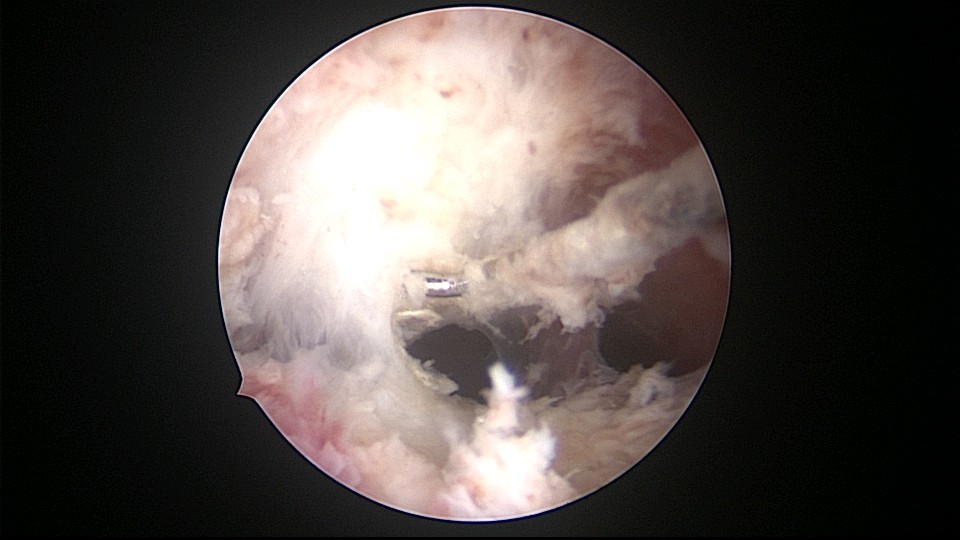

患者34岁,G4P1,顺产1次,继发不孕,宫腔容积小,宫腔粘连。2020年9月宫腔镜探查,见宫腔下段幕状粘连,两侧小孔与宫腔上段相通,形成假的输卵管开口。双极电针切开粘连,宫腔形态恢复正常,显露双侧输卵管正常开口。2020年10月宫腔镜二探取球囊,宫腔形态正常,双侧输卵管开口可见。2021年6月自然妊娠,2022年2月足月剖宫产分娩,2023年5月再次妊娠1次,人流终止妊娠。现39岁,G6P2,顺产1次,剖宫产1次。